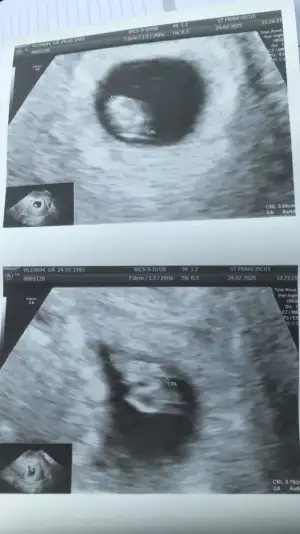

Ayyy çok anlamıyorum ben bunlardan ama boş gebelikten şüphelenşyordunn gördün mü bebişleriiiiiiiiii canmm

Evet gördümmmmAyyy çok anlamıyorum ben bunlardan ama boş gebelikten şüphelenşyordunn gördün mü bebişleriiiiiiiiii canmm

Ah süper görmüşsün çok sevindim kalp atışında baktımı direk ? Gözün aydın canımKurban olurum bunları vereneee![]()

Tşk ederim canımm kalpleri gördü ama kalpleri duymak için 2 hafta sonraya randevu verdiAh süper görmüşsün çok sevindim kalp atışında baktımı direk ? Gözün aydın canım

Ama göründü dimi kalp sende gördün minicik pıt pıt atıyor .. maşallah bak ikizlerde böyle geç görünme olabiliyormuş gözün aydın canım .Tşk ederim canımm kalpleri gördü ama kalpleri duymak için 2 hafta sonraya randevu verdi![]()